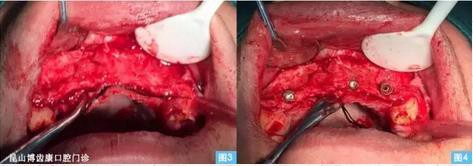

圖3圖4:(左圖3)牙槽嵴頂偏腭側(cè)水平切口,雙側(cè)附加切口翻開全厚粘骨膜瓣至鼻底,清晰暴露術(shù)區(qū)。(右圖4)小球鉆定位,擴(kuò)孔鉆依次備洞,植入植體 ,可見13、23唇側(cè)骨壁缺損嚴(yán)重 。

圖5圖6:在骨缺損區(qū)周圍用小球鉆制備多個營養(yǎng)孔(可為骨再生提供良好的血運)將生理鹽水與骨替代材料混合后覆蓋于骨缺損區(qū),再放置鈦膜,再修剪生物膜覆蓋于i-Gen鈦膜上。骨增量以后原有的軟組織量不足,需要增加軟組織的游離度,在唇側(cè)粘膜瓣底做減張切口,無張力的關(guān)閉牙槽脊頂?shù)那锌冢ㄖ踩肱ち?5牛 50轉(zhuǎn))。